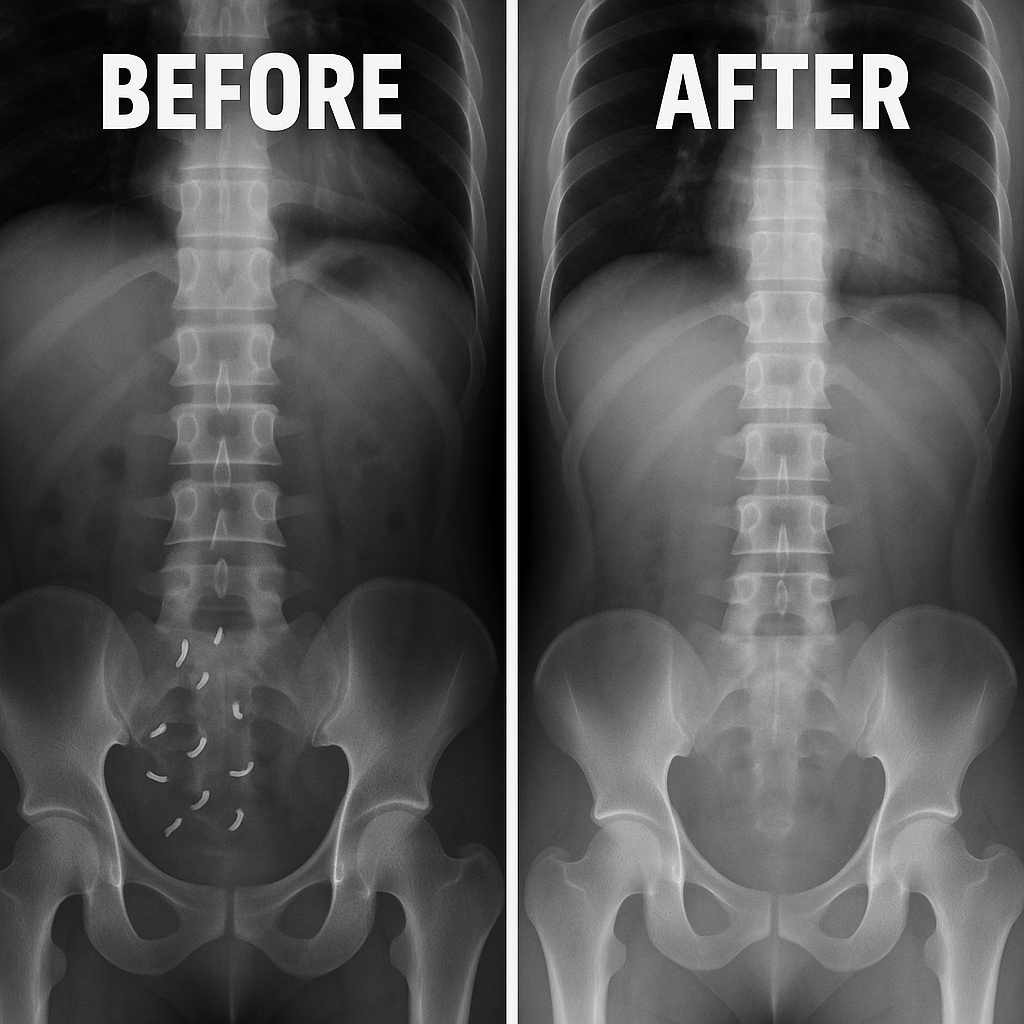

Your Journey to A Parasite Free Life

With just a few capsules, you'll gently detox, restore balance,

and start feeling like yourself again.

Noticeable Relief Begins

Early signs of change: reduced bloating, smoother digestion, and better energy throughout the day. You may start to feel lighter—physically and mentally.

Balance in Motion

As internal systems recalibrate, gut and immune functions become more stable. Brain fog lifts, energy stays more consistent, and your mood feels more even.

Full-Body Reset

This is where it all comes together—improved focus, stronger immunity, and a more resilient digestive system. You feel more vibrant, clear, and in control of your wellness.